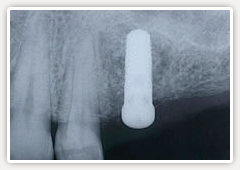

【術後】

予定通り、骨が再生してきています(レントゲンで白くもやもやしたところが骨です。黒い部分は骨が無い状態)骨再生を確認後インプラント治療ができました。